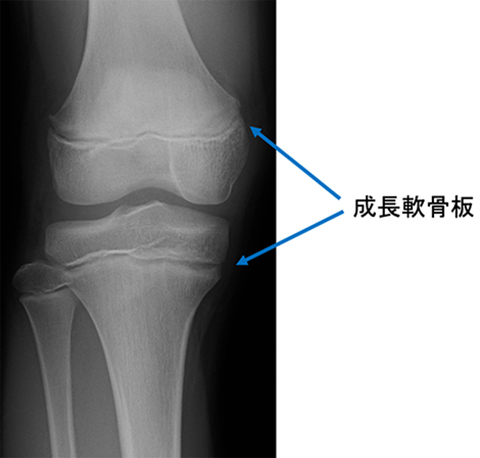

私たち人間の骨は全部で206個ありますが、赤ちゃんの時には約350個もの骨が認められています。骨といっても分離骨といわれ長い時間をかけて一部つながりあって、成人した段階で206個になります。骨の成長が終わるのは女性で15~16歳、男性で約18歳といわれています。身長の伸びは、10歳ころまでは1年に約6cm、思春期の初期(男子は10.5〜14歳、女子は10~13歳)になると1年に6~8cm、青年期中期(男子は12~14歳、女子は12.5~15歳)になると最も急激な成長を遂げる段階で女子で約8cm、14歳の男子で約10cmも伸びます。成長期の子供の骨をX線で撮影する、関節付近に「成長軟骨板(骨端線)」と呼ばれる線があります。この線は骨の両端部分にある骨端と骨幹との境目部分にあたり、成長期の子供しか確認できません。

この成長軟骨板部分にある組織は「骨端軟骨」と呼ばれる軟骨組織で形成されています。

骨端では、新しい骨を作る骨芽細胞と、古い骨を分解・吸収する破骨細胞が盛んに働いています。成長期には骨芽細胞の働きが活発化するため、この骨端軟骨組織が増殖しながら栄養素を取り込んで硬い骨へと置き換わっていきます。骨は成長軟骨板に沿って伸びていきます。

成長期が終わりに近づくにつれ軟骨層は少なくなり、やがてすべての軟骨層が硬い骨へと置き換わると、成長軟骨板はほとんど見えなくなります。この段階で骨の伸びが止まり、身長も伸びなくなります。X線で成長軟骨板が確認できるかどうかが、成長期を知る分かりやすい目安になります。